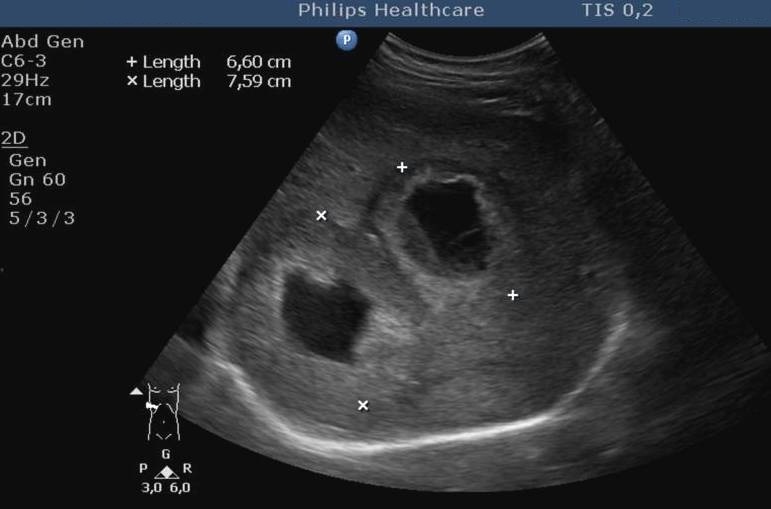

14.5.5. Cysts

The spleen cysts occur less frequently then the liver cysts, their morphological appearence is similar to that of the liver cysts (homogeneous, cystic content, sharp contour, thin wall, sometimes some thin septa). Most of them is detected only accidentally. It has a therapeutic consequence if its size increases resulting symptoms for the patient by the compression of the sorrounding tissues (Figure 47, 48).

Figure 47: Spleen cyst, US

Figure 48: Spleen cyst, contrast enhanced CT